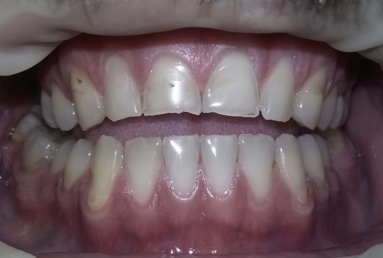

Then fixed orthodontic treatment is set for almost 2 years, so moving the teeth a new more favorable position is obtained to create space for veneers. After wax up a mock up is done for provisional veneers and the new occlusion is tested.

The final porcelain veneers for all frontal maxillary teeth are completed with tooth whitening and changing some composite fillings in lower frontals. On the lower left side a dental implant is inserted, on the upper right side external sinus lift is done. the treatment will be finalised with another upper implant, then two crowns on implants.